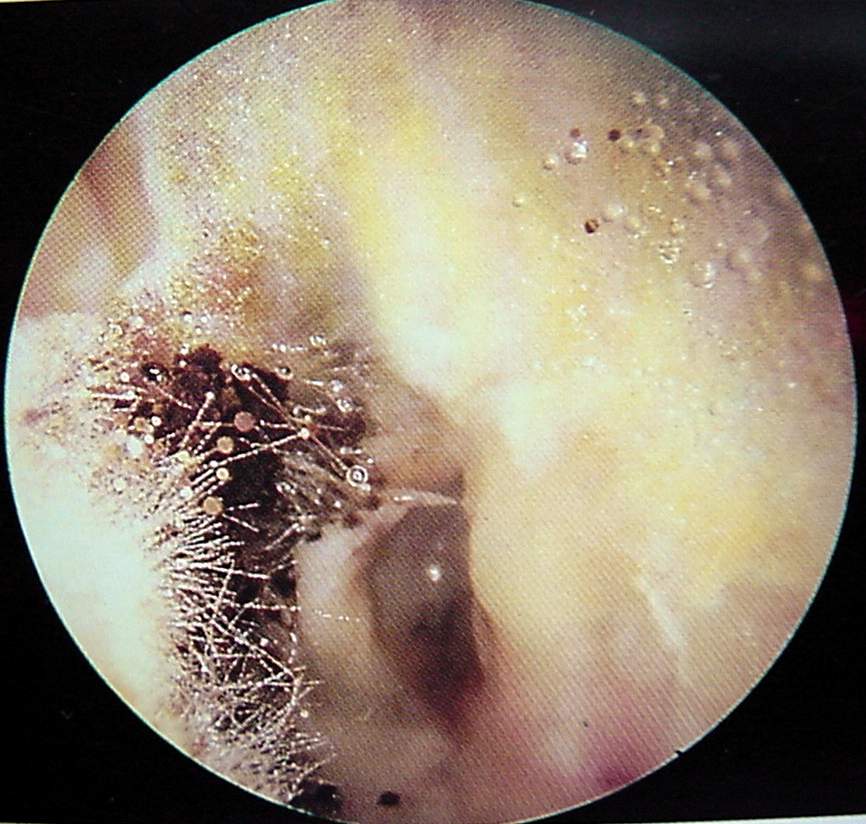

Ear Clinical Photos for Static Stations